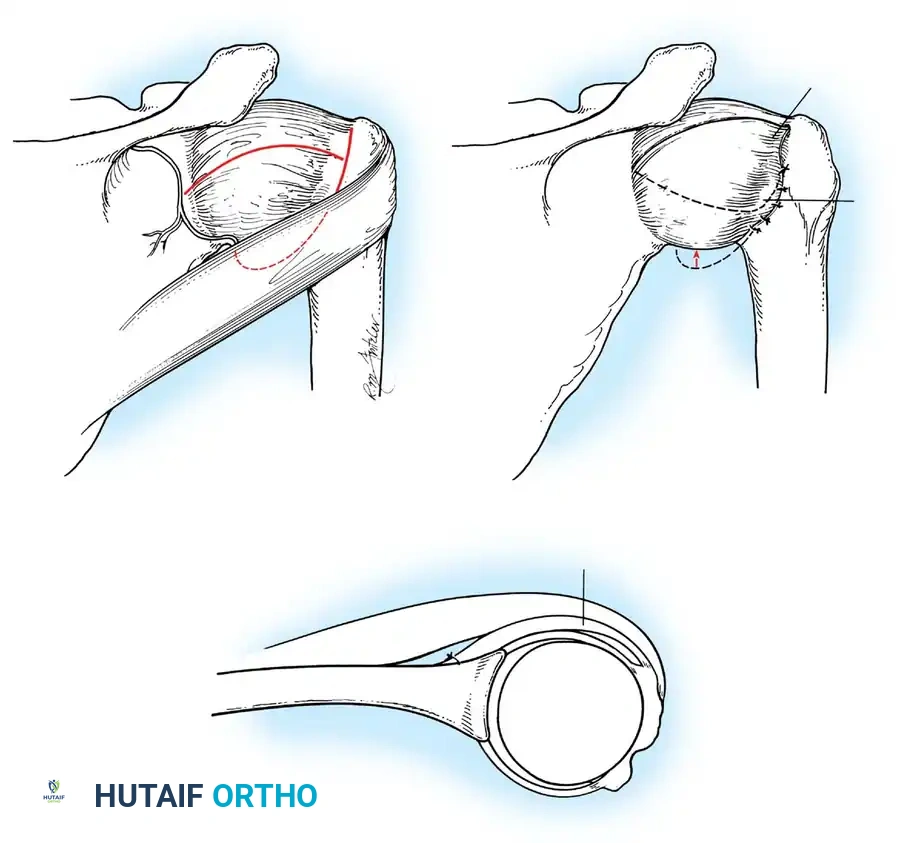

- Inferior Glenohumeral Ligament (IGHL) Complex: The most critical static stabilizer. It attaches to the glenoid margin from the 2-o’clock to 3-o’clock positions anteriorly, extending to the 8-o’clock to 9-o’clock positions posteriorly. Its humeral attachment lies below the articular margin on the anatomical and surgical neck. O’Brien et al. described this complex as a "hammock-like" structure consisting of a thickened anterior band, a posterior band, and a thinner axillary pouch.

CLINICAL PEARL: The biomechanics of the IGHL complex are dynamic. With external rotation and abduction, the hammock shifts anteriorly and superiorly; the anterior band tightens to prevent anterior translation, while the posterior band fans out. Conversely, internal rotation tightens the posterior band. The anteroinferior band is the primary restraint to anterior translation at 90 degrees of abduction and external rotation (the classic apprehension position).

Turkel et al. demonstrated that true anterior dislocation cannot occur if the IGHL remains intact. Furthermore, Warren introduced the "circle concept," proving that for significant anterior translation to occur, there must be concomitant disruption or plastic deformation of the posterior capsular structures.

The musculature surrounding the shoulder provides essential dynamic stability. The deltoid produces primarily vertical shear forces, tending to displace the humeral head superiorly. To counteract this, the intrinsic muscles of the rotator cuff provide compressive forces. Lippitt and Matsen described "concavity compression," wherein the dynamic contraction of the rotator cuff compresses the humeral head into the concave glenoid socket. Loss of the labrum reduces this stabilizing effect by up to 20%.

The essential step in restoring stability is the anatomical reduction of the capsulolabral complex to a bleeding bone bed on the anterior glenoid rim.

- Debridement: The anterior glenoid neck is decorticated using a motorized burr, rasp, or osteotome to create a bleeding cancellous bed. This promotes robust biological healing of the repaired labrum.

- Mobilization: The scarred, medially displaced labrum (ALPSA lesion) must be fully mobilized using a periosteal elevator until the subscapularis muscle belly is visible anteriorly. The tissue must float freely to be shifted superiorly and laterally.

- Anchor Placement: Suture anchors (typically 3 to 4) are placed along the articular margin of the anteroinferior glenoid (from the 5:30 to 3:00 positions for a right shoulder). Anchors must be inserted at a 45-degree angle to the articular surface to maximize pullout strength and avoid joint penetration.

Capsular Shift and Closure

To address capsular redundancy, an inferior capsular shift is performed.

- The arm is positioned in 30 to 45 degrees of abduction and 20 degrees of external rotation.

- The inferior capsular flap is advanced superiorly and laterally, tensioning the IGHL complex. The sutures from the anchors are passed through the shifted capsule and tied.

- The superior flap is then brought down over the inferior flap in a "pants-over-vest" fashion to reinforce the anterior wall and close the rotator interval.